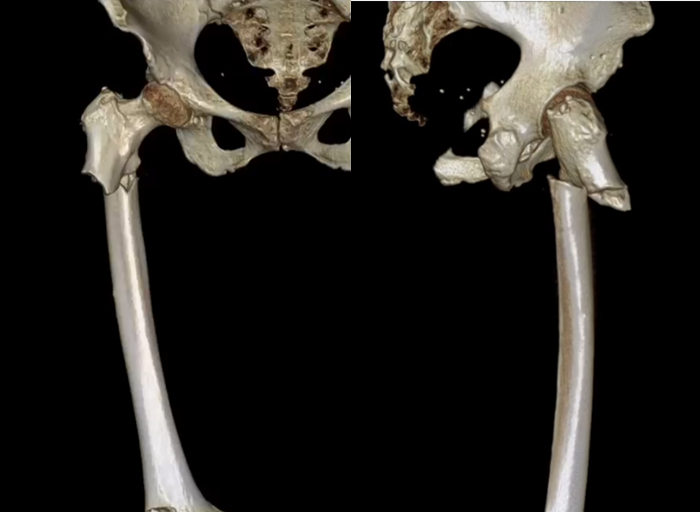

骨三維成像成像

非典型股骨骨折是由長期服用雙磷酸鹽藥物導致的股骨干部骨折,其特點與創(chuàng)傷性股骨干骨折完全不同。骨折好發(fā)部位:骨折位于股骨干部,股骨小轉子以下,股骨髁以上。

手術治療:手術治療對于完全性非典型股骨骨折主要有髓內釘治療以及鋼板內固定治療。其中髓內釘固定可靠。但部分老年人股骨前弓過大,不適宜用髓內釘固定。本例患者股骨前弓較大,但尚可用髓內釘固定。術后股骨正常前弓減小。術后時間尚短,還需繼續(xù)隨訪。